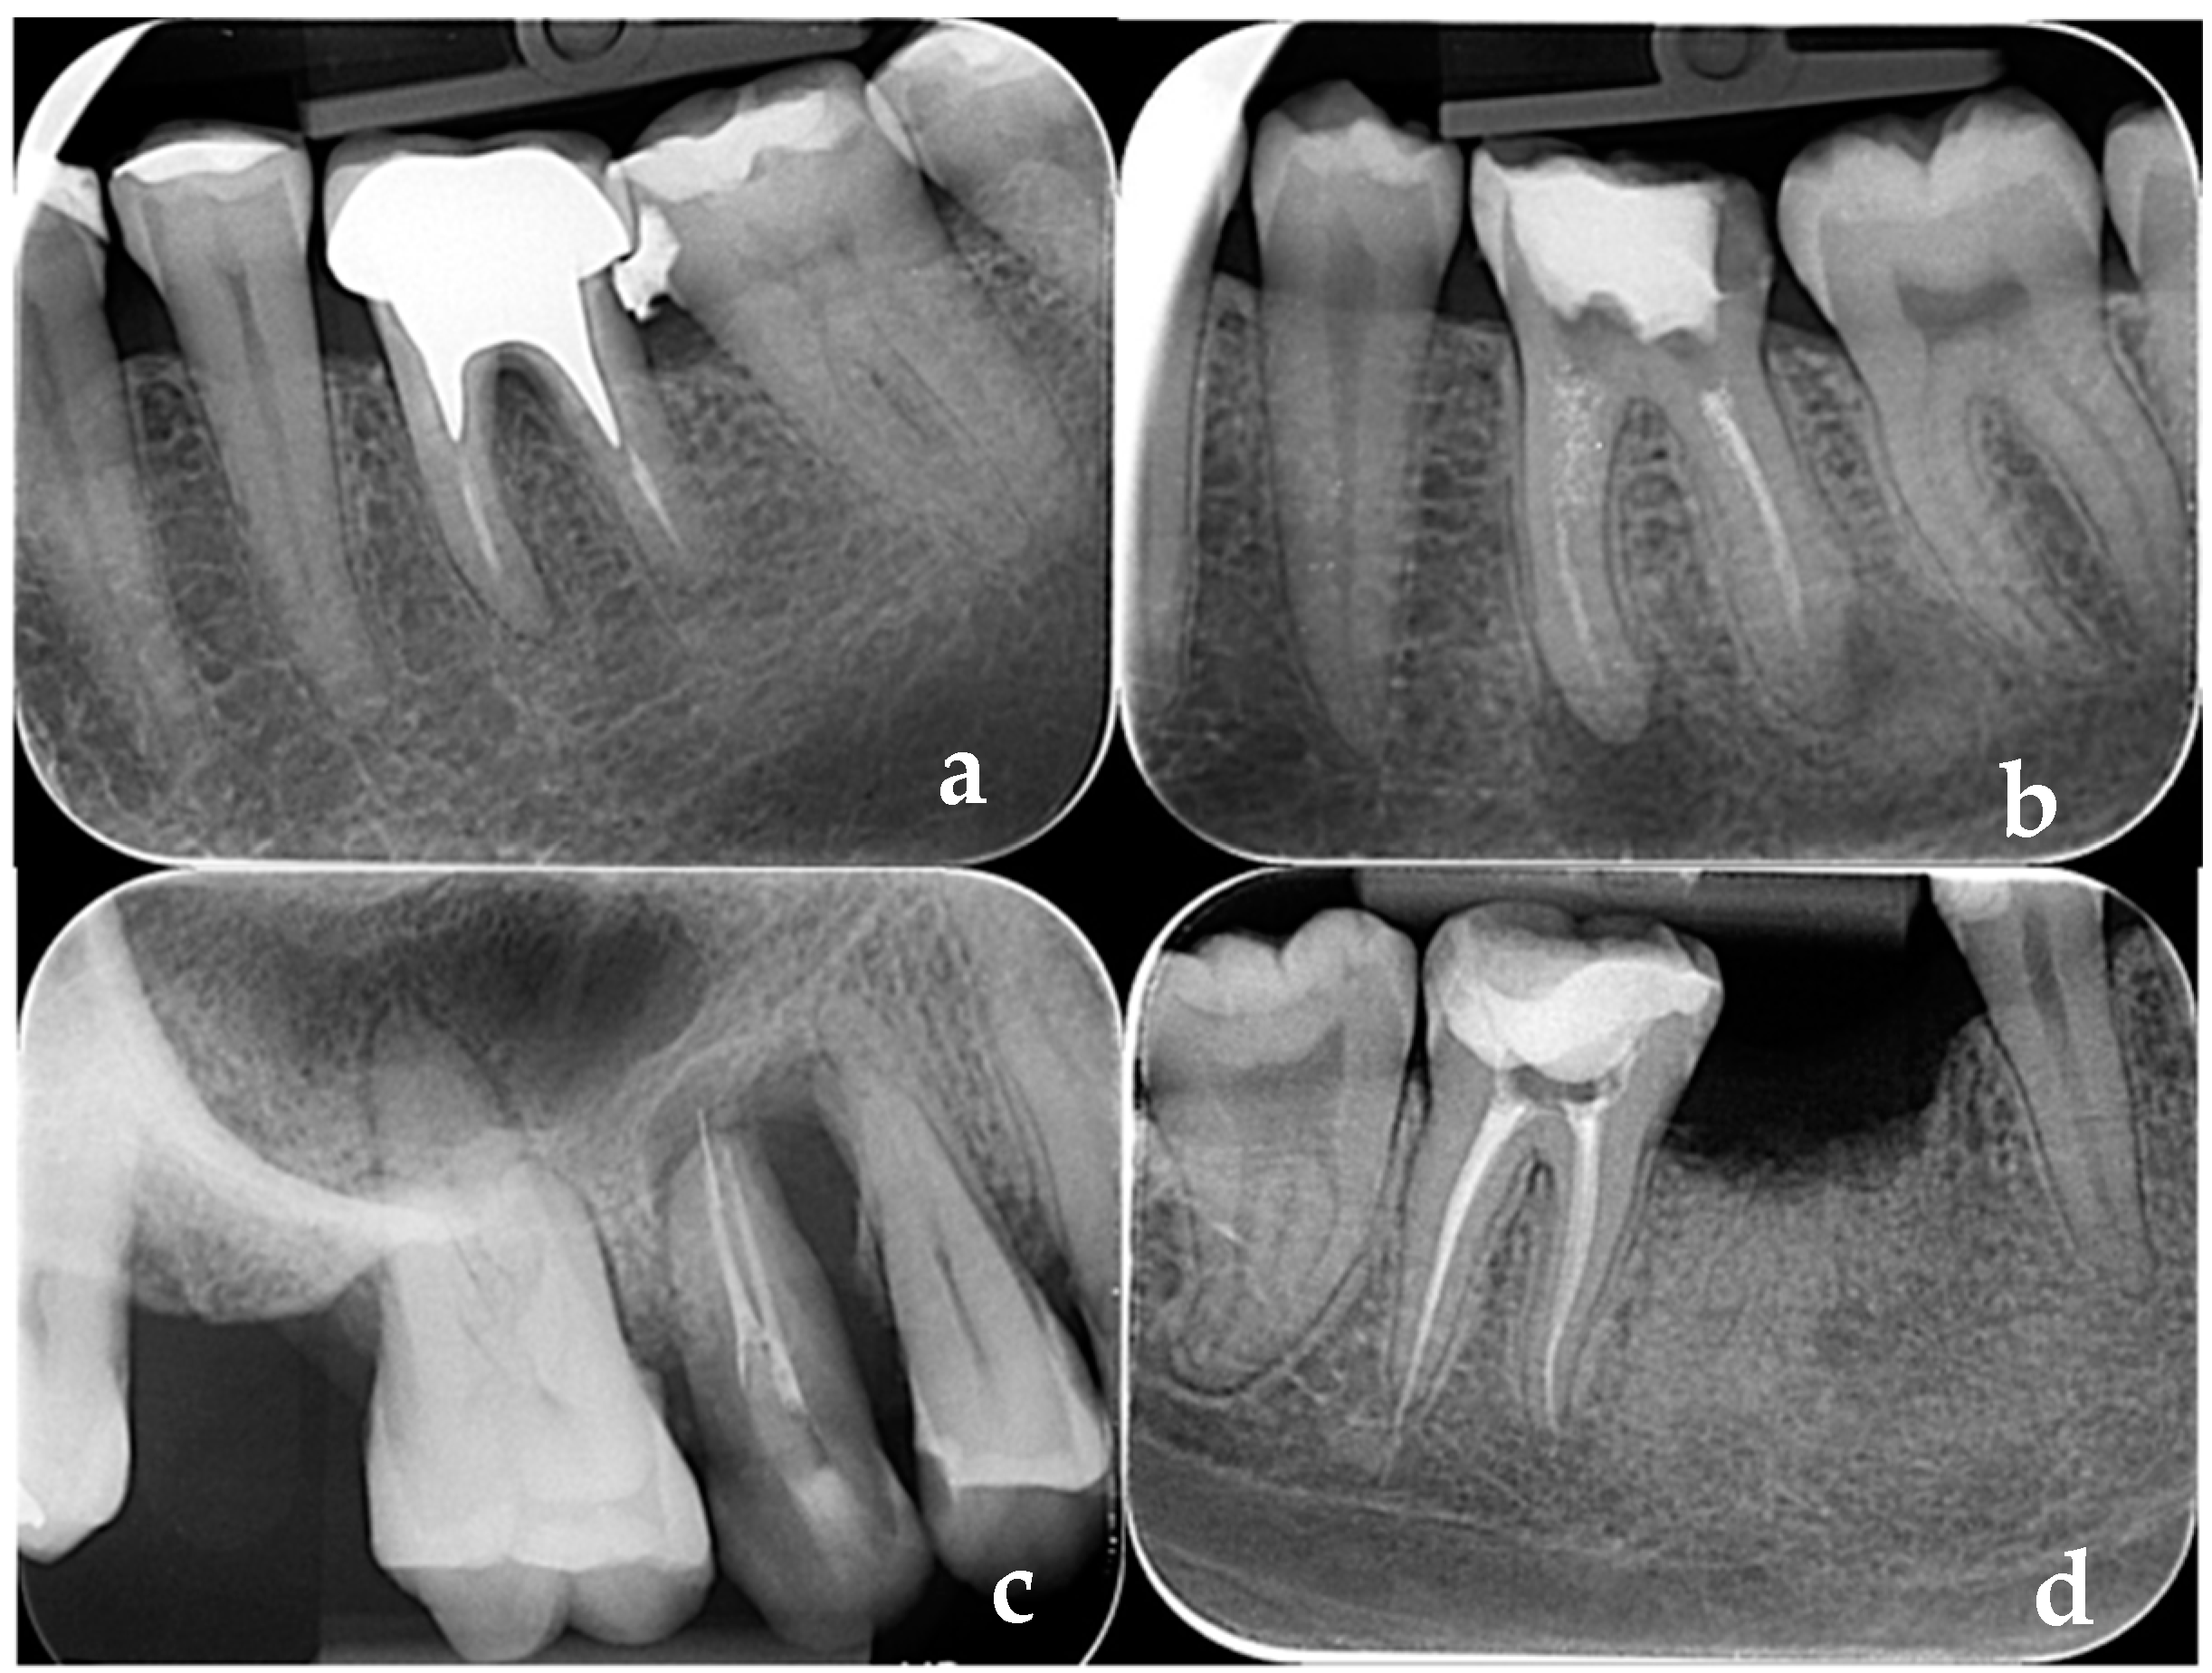

- Sălceanu, M.; Vataman, M.; Aminov, L.; Giuroiu, C.; Topoliceanu, C.; Decolli, Y.; Ghiorghe, C.-A.; Melian, A. Diagnosis and follow-up of the periapical lesions in the non-surgical endodontic treatment: A CBCT study. Rom. J. Oral Rehabil. 2017, 9, 32–36. [Google Scholar]